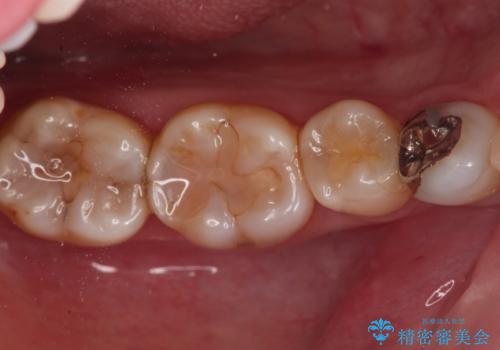

銀歯を目立たなくしたい セラミックインレーでの治療

- 外から見える範囲の銀歯のやり替えをご希望で来院されました。

セラミックインレーでの治療となります。

奥歯とはいえ今回のようなケースでは笑った時に銀歯がちらつきます。